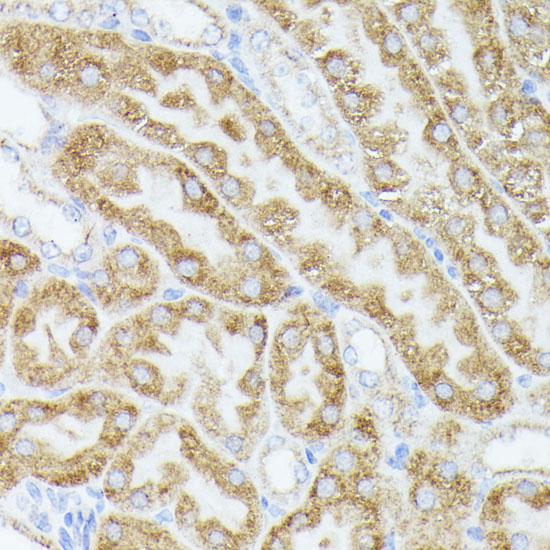

Immunohistochemistry of paraffin-embedded rat ovary using ACAT2 at dilution of 1:100 (40x lens).

Immunohistochemistry of paraffin-embedded mouse kidney using ACAT2 at dilution of 1:100 (40x lens).